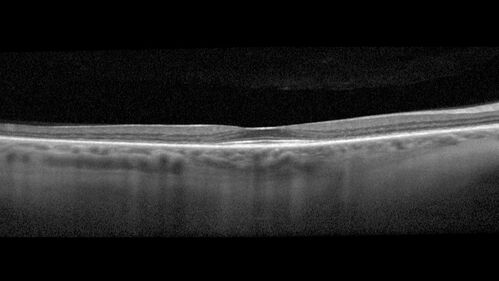

Hydroxychloroquine Toxicity

60 year old female received 6.5 mg/kg Plaquenil for 15 years and developed toxicity. VA 20/40 OD, 20/20 OS